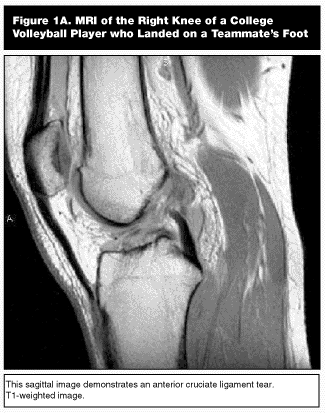

Radiography of the knee is essential in these injuries to evaluate for fractures or avulsed ligament insertions.9,10,14,17,19 Stress radiographs can also be helpful in diagnosing ligament instability. MRI can be very useful in evaluating the knee ligament structures although it is not essential if a careful physical examination can be performed.9,10,12 (see Figures 1A-B). MRI is also sensitive in diagnosing associated meniscal pathology in addition to ligamentous injuries.9,14,17,20,21